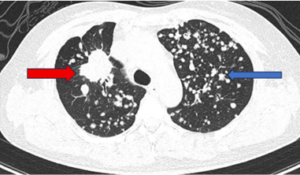

CASE LÂM SÀNG ĐIỀU TRỊ UNG THƯ PHỔI KHÔNG TẾ BÀO NHỎ ÂM TÍNH VỚI PD-L1

CASE LÂM SÀNG ĐIỀU TRỊ UNG THƯ PHỔI KHÔNG TẾ BÀO NHỎ ÂM TÍNH VỚI PD-L1 GS.TS Mai Trọng Khoa 1,2, PGS.TS Phạm Cẩm Phương 1,2, TS.BS Phạm Văn Thái1 BSNT. Phùng Thế Thông2 1Trung Tâm Y học hạt nhân và Ung bướu, Bệnh viện Bạch Mai 2Trường Đại học...